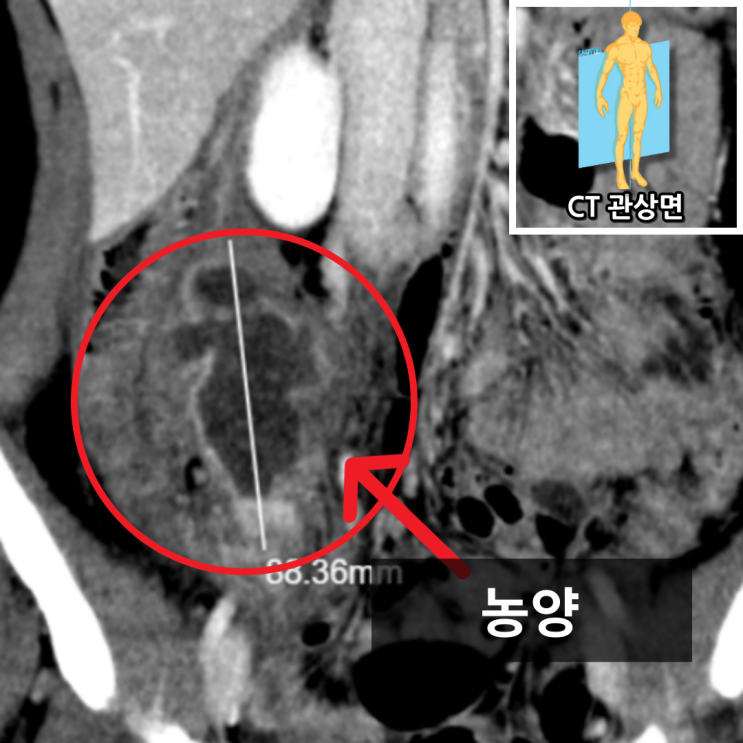

피 검사상 백혈구와 염증 수치가 높았습니다(WBC 14.81, CRP 11.43). 정밀 검사가 필요하다고 생각되어 복부 CT를 촬영하였습니다. CT 사진을 보면 충수는 잘 보이지 않고, 8.8cm크기의 농양으로 생각되는 부분이 보입니다. 급성 충수염이 시간이 지나가면서 천공이 되고 주변으로 농양을 형성한 케이스입니다.

• 복부CT: 8.8cm 농양 확인 (빨간 동그라미, CT 관상면) 복부CT: 8.8cm 농양 확인 (빨간 동그라미, CT 관상면)